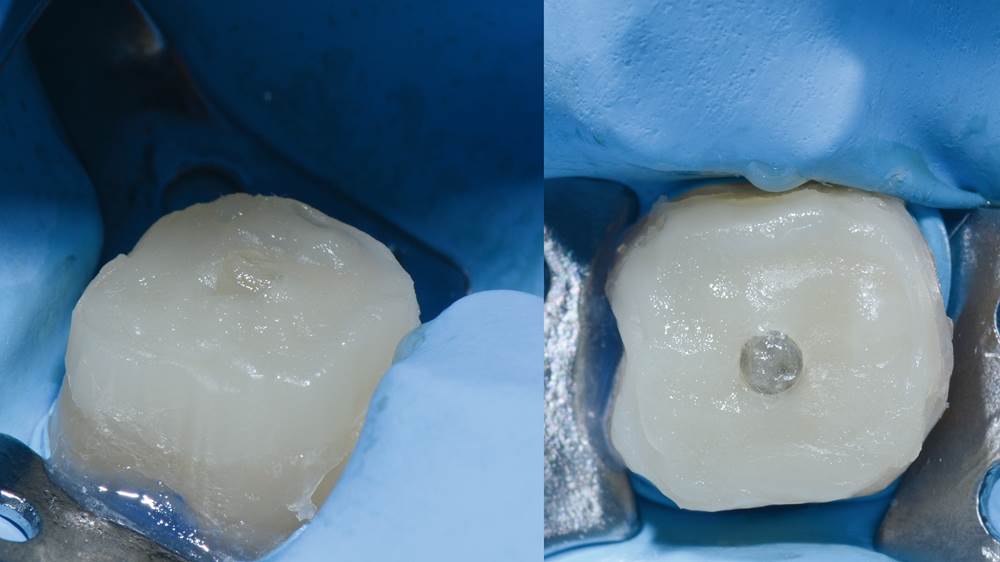

8. Yhdistelmämuovipilari valokovetuksen jälkeen.

9. Lopullinen hionta.

18. Lopputulos (okklusaalinen näkymä).